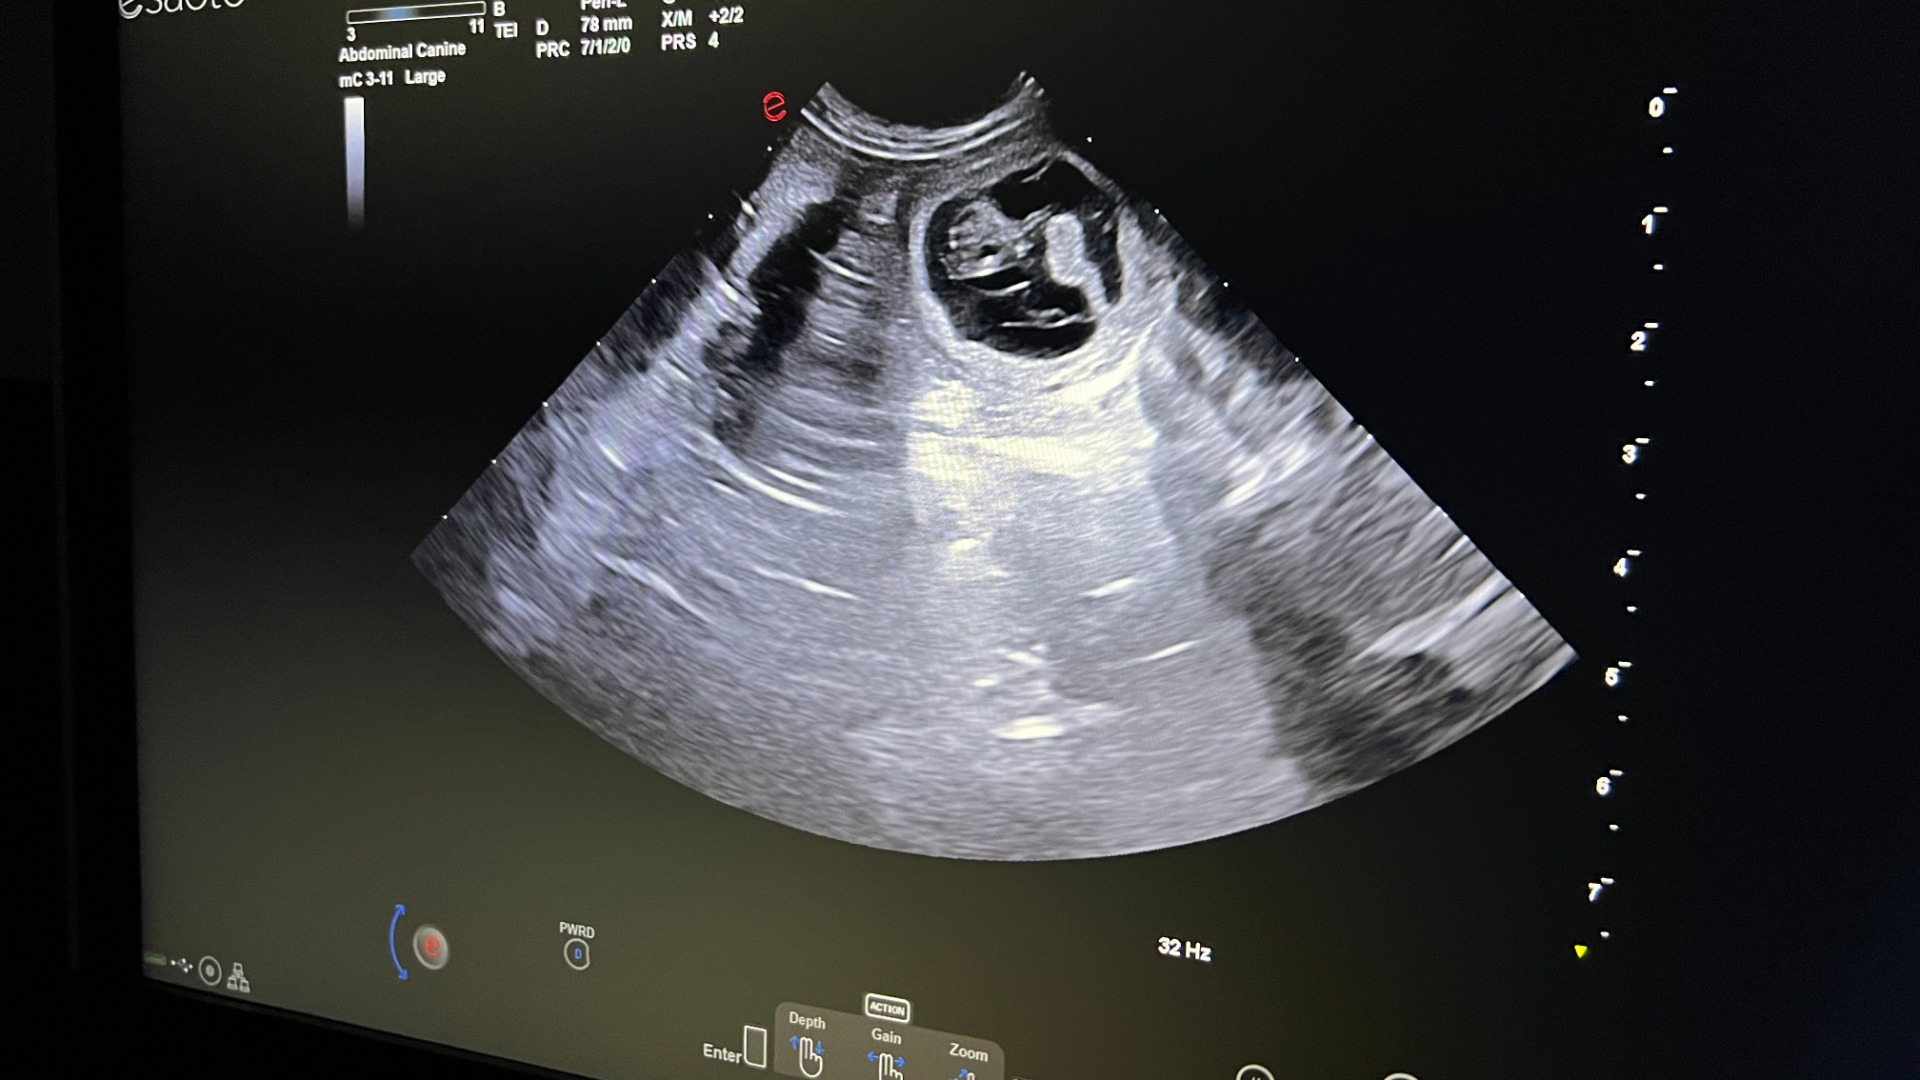

Štěňátka mají 1 týden a mají svoje první video.